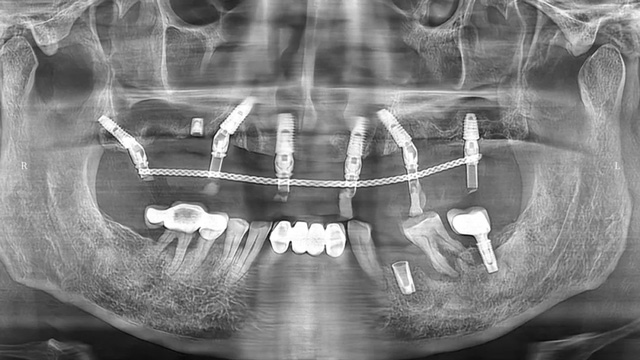

经过检查,余国庆医生发现吴叔叔的口腔情况比较复杂。检查报告显示,他口腔里现存完整的种植牙只有两颗,上下颌各1颗。

“上面种了4颗,断了两颗,脱落1颗,只有1颗能用,下面有一颗牙冠脱落,另一颗有种植体周围炎,有明显的骨吸收。”吴叔叔剩下的天然牙也不好,做了几处修复,之前的牙冠修复用的都是烤瓷牙,有好几颗磨损严重露出了金属。由于存在缺牙、不良修复体等情况,口腔整体咬合紊乱,进食很困难。

治疗前口腔全景片